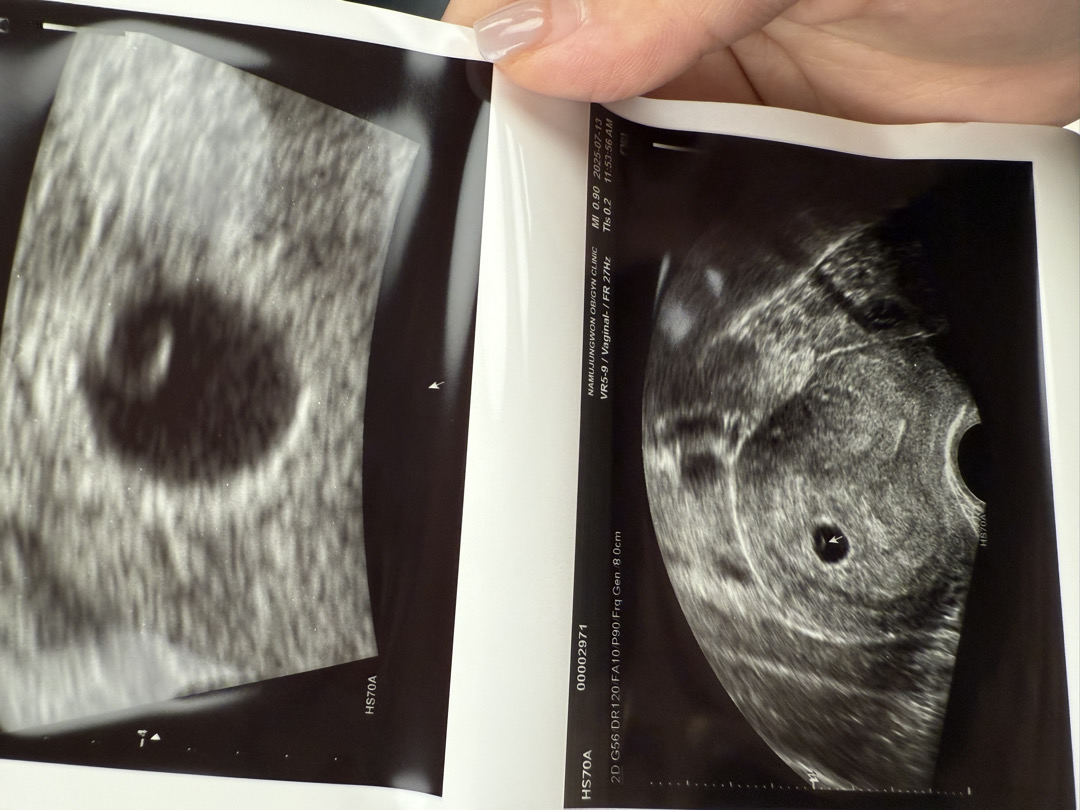

난황보고왔어요 !!

5주6일차때 촘파로 난황보고왔는데 아기가 있는걸까요?!!🥹

아직은 안보이죵!

ㅠㅡㅠ얼른 보고싶어요ㅎㅎㅎ